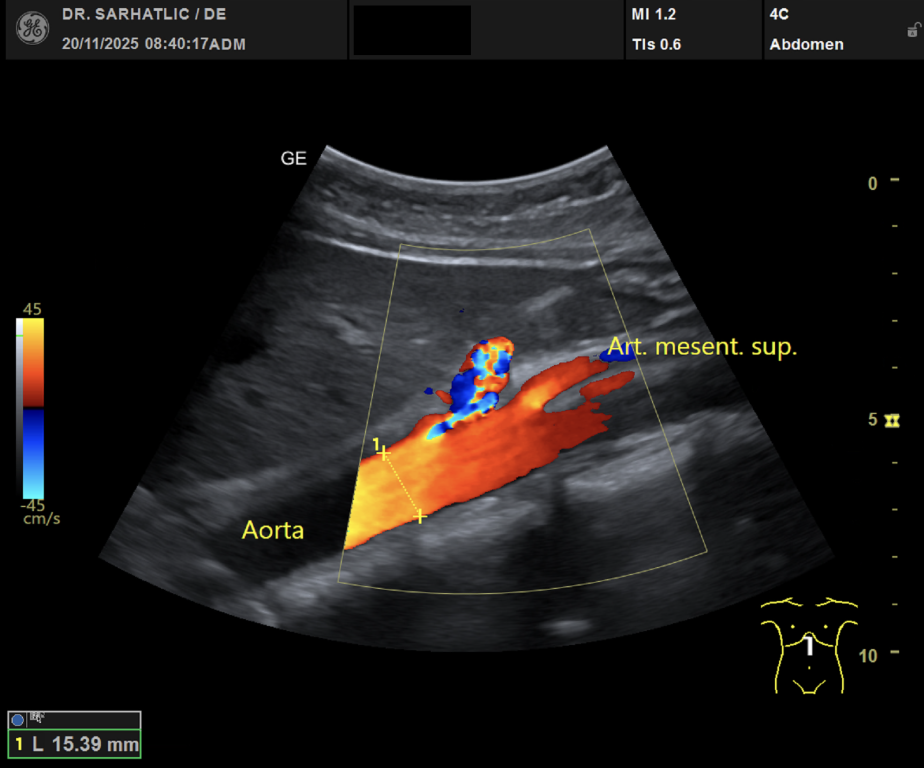

MODERNE ULTRASCHALLDIAGNOSTIK- Modernes Farbdoppler-Ultraschallgerät

- Hochauflösende Schallköpfe

- Detaillierte Organuntersuchungen

- Ultraschall aller inneren Organe (z. B. Leber, Bauchspeicheldrüse, Nieren, Prostata, Schilddrüse)

- Ultraschall der Gefäße (z. B. Halsschlagadern)